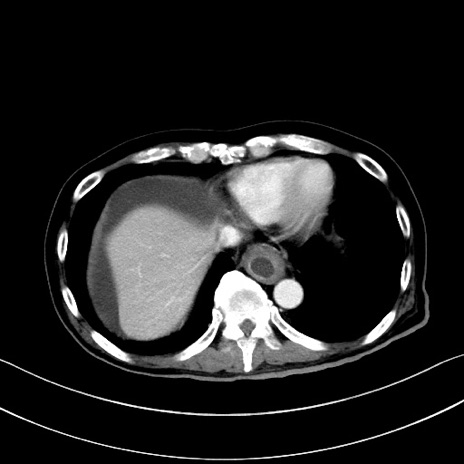

症例28(横断像)

【症例】60歳代男性

【主訴】嘔吐

【現病歴】胃癌にて胃全摘後。食思不振が悪化し、夜中に嘔吐することがある。

【既往歴】胃癌、胃全摘、脾摘、胆摘後

【データ】WBC 5900、CRP 10.56